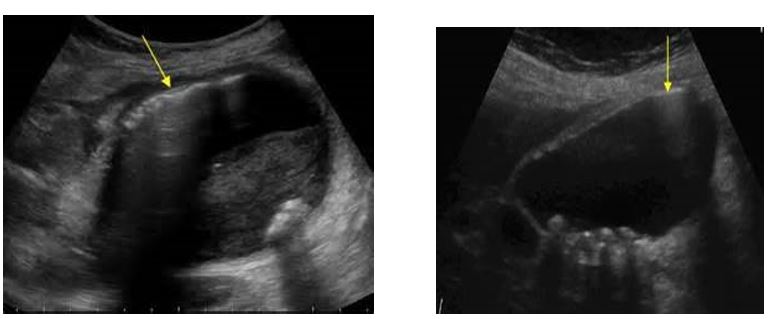

Sludge

This echogenic material has the following three characteristics

Does not cause shadowing

Is not gravity-dependent

Does not show a layering effect

sludge

patterns of sludge